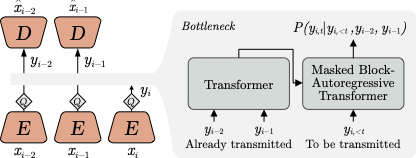

Ongoing work involves addressing the deficiencies of classical codecs in preserving medically relevant information. Our primary proposed solution is to leverage data-driven or “learned" compression using the recent Video Compression Transformer model [10]. This model shows especially useful properties, such as the ability to capture domain-specific synthetic camera motion and domain-specific texture characteristics. We also plan to explore the complex relationship between training on videos compressed using one algorithm (e.g. H264 QP20), but run on a different type of compression during inference (e.g. lossless).